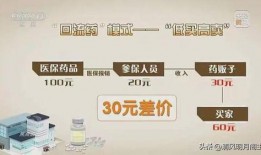

囤药贩子爆料犯法吗视频,违法还是无奈之举?

亲爱的读者们,你是否曾在疫情期间,对那些囤积药品、高价售卖的现象感到愤慨?最近,一位自称是“囤药贩子”的人在网上爆料,引发了广泛...

2025-07-24 306 -